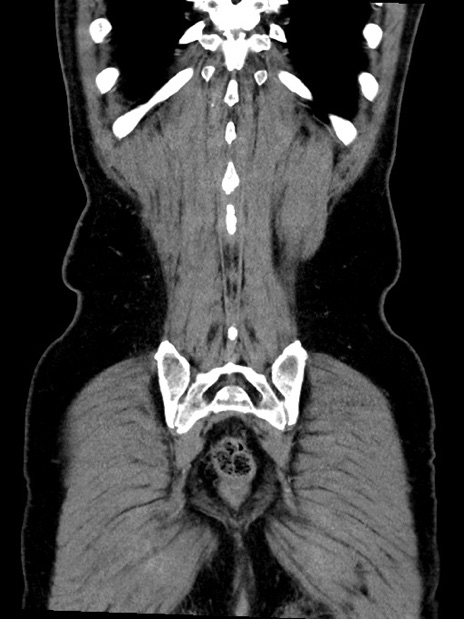

症例35(冠状断像)

【症例】70歳代 男性

【主訴】腹部膨満、嘔吐

【現病歴】昨日より腹部膨満感出現。本日増悪し、仙痛出現。嘔吐あり、受診。

【既往歴】糖尿病、胆摘後

【身体所見】BP 149/80mmHg、HR 74/min、BT 35.9℃、腹部:膨満、軟、圧痛なし。腸雑音減弱あり。上腹部正中切開瘢痕あり。

【データ】WBC 13500、CRP 1.72